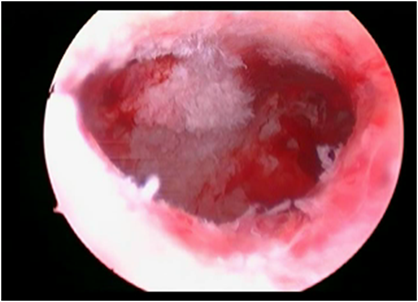

2.Septate Uterus

ह्यामध्ये गर्भाशयात पडदा निर्माण झालेमुळे गर्भाशय दुभंगले जाते.हा पडदा दुर्बिणीद्वारे ऑपरेशन करुन काढला जातो.ह्याला Septurm Excision म्हटले जाते.आपल्या हॉस्पिटलमध्ये अशाप्रकारे पडदा काढल्यानंतर बऱ्याच जणांना त्याचा लाभ झाला आहे.

septate uterus

ऑपरेशनपूर्वी